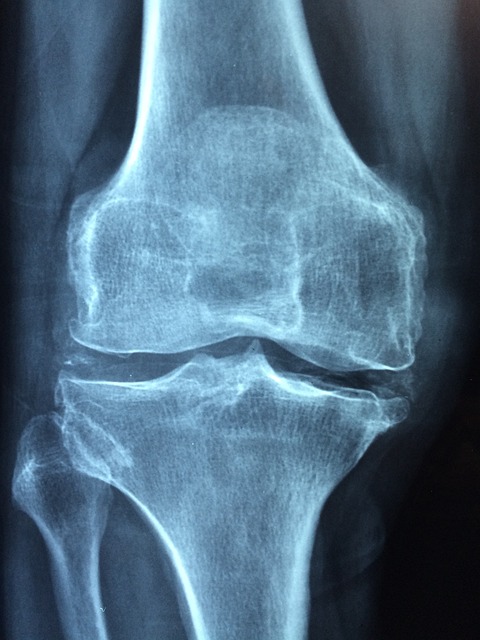

1. 퇴행성 관절염

노화에 따라 관절 연골이 닳고 뼈끼리 마찰되면서 염증과 통증이 생긴다. 특히 무릎, 고관절, 손가락 등 사용이 많은 부위에서 흔하다.

- 관절이 움직일 때마다 소리(크레피투스)가 나고 아프면 연골 마모 가능성 있음